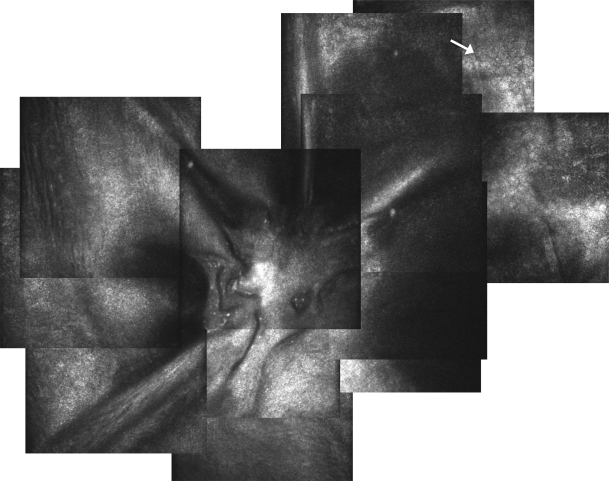

Fig. 5

In vivo confocal microscopy of the perforation site in case 2 taken 6 months after deep anterior lamellar keratoplasty. Tractional folds in Descemet’s membrane exerted by the attached iris strand can be seen. No endothelial cells are present in the center, but can be seen in the periphery of the image at a measured distance of 600 µm from the perforation site

A 31-year-old man was referred with a history of a perforated left corneal ulcer secondary to bilateral rosacea keratitis and iris plugging of the corneal perforation. He had had repeated corneal glueing over 1 year prior to referral, but the leak kept recurring. He presented with a corneal scar with thinning and spontaneous leakage at the site of perforation with the iris adherent to and around the wound (Fig. 3a). VA was 6/12 with a pinhole. After 7.5-mm partial thickness trephination of the recipient cornea, lamellar dissection was performed with a crescent blade. An air infusion was used to maintain the anterior chamber. The perforation site was spared until completion of the centripetal dissection of the unaffected posterior corneal stroma surrounding the edge of the perforation as in case 1. The iris strands remained adherent to the posterior edges of the perforation. A 7.75-mm donor cornea button was stripped of DM and sutured to the recipient bed with partial-thickness, combined, interrupted 10-0 nylon sutures and a continuous 11-0 Prolene suture. Postoperative topical treatment was identical to case 1. Clinical examination on day 1 showed mild corneal edema and no double anterior chamber. The cornea cleared over the following 4 weeks and at 6 months BCVA was 20/32. The iris remained at the edges of the former perforation site (Fig. 3b). AS-OCT confirmed a central 115-µm pre-descemetic stromal layer and a 29-µm scarred stromal layer at the perforation site (Fig. 4). IVCM was performed and confirmed traction folds in DM caused by the attached iris strands with absent endothelial cells in this region (Fig. 5). Intact endothelial cells were found starting at a distance of 600 µm from the perforation site. Central ECD was 2,421 ± 18 cells/mm2 using IVCM at a focal depth of 568 µm.